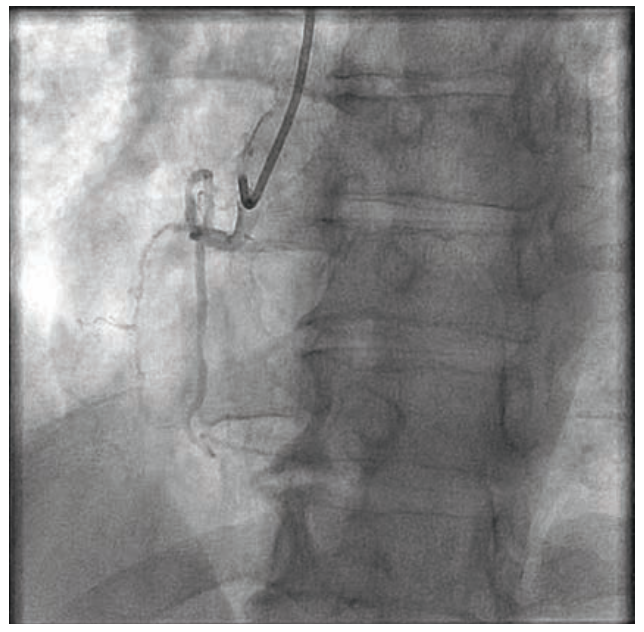

Owing to the patient’s anginal symptoms and ischemia inferiorly on the Cardiolite imaging, it was elected to open the RCA CTO. An Amplatz Left 1 6 French (Fr) guiding catheter was placed into the anterior takeoff RCA. A Turnpike Spiral microcatheter (Teleflex) with an .014-inch Minamo wire (Asahi Intecc) was initially chosen but could not traverse the stenosis, so the wire was replaced with an .014-inch Sion black wire (Asahi Intecc). This wire appeared to be extraluminal, and was removed and replaced with an .014-inch Mongo wire (Asahi) in the distal vessel, which appeared to track in the true lumen (Figure 2). A 6 Fr GuideLiner (Teleflex) was placed, but in trying to ascertain distal wire position with an injection into the GuideLiner, the vessel appeared to be dissected (Figure 3). We could see the main channel distally, and therefore took a new Minamo 300 wire and placed it into the true lumen. The Mongo wire was removed. However, the Minamo wire would not traverse into the distal vessel, so it was changed for an .014-inch Choice PT Floppy wire (Boston Scientific), which was successful in going distally. We placed a Sasuke dual lumen 145 microcatheter (Asahi Intecc), removed the Choice PT wire, and placed a Balance Middle Weight (BMW) Universal 300 wire (Abbott Vascular). A GuideLiner had been used for support and we attempted to place a Synergy 3.5 mm x 48 mm stent (Boston Scientific). However, the stent would not go forward. It was removed and found to be intact on inspection. The stent was replaced with a 3.0 mm x 30 mm Monorail Emerge balloon (Boston Scientific) for further dilatation of the RCA to 6 atmospheres (atm) for overlapping 15-second inflations. A third inflation of 12 atm for 35 seconds was performed and the balloon was removed. A 3.0 mm x 38 mm Synergy drug-eluting stent (Boston Scientific) was not able to be placed adequately distally, and was removed, inspected, and found to be intact. It appeared that the GuideLiner might be preventing some forward motion of the stent and it too was removed. There was, on angiography, a flow abnormality consistent with a small branch wire perfusion abnormality. There was no clear-cut staining. An echo showed no evidence of pericardial fluid and no tamponade physiology. It was felt that this should be addressed and so a 1.5 mm x 12 mm Takeru balloon (Terumo) was inflated to 6 atm for 20 seconds, though this did not resolve the flow abnormality. Ultimately, a 2.5 mm x 15 mm PK Papyrus covered stent (Biotronik) was delivered to the site of flow abnormality and deployed to 6 atm for 60 seconds. Angiography after balloon deflation showed no further flow into the branch (Figure 4).